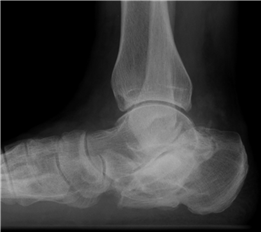

Clinical & Radiographic Imaging Archive

Clinical Image